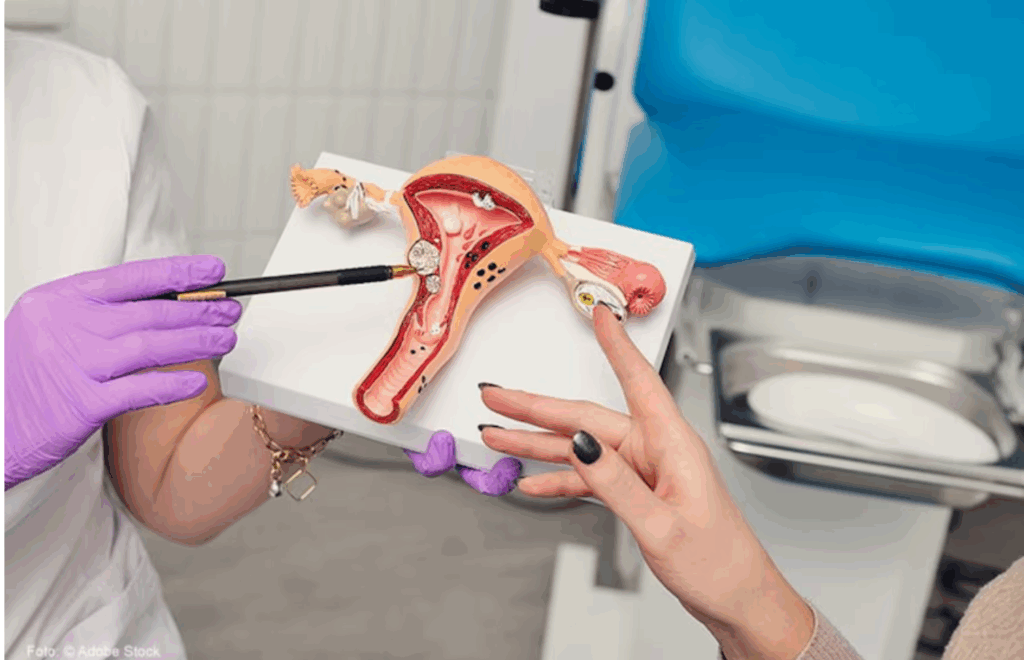

El síndrome de ovario poliquístico cambia de nombre: ahora será reconocido como un trastorno metabólico y endocrino

Durante años, millones de mujeres vivieron síntomas como menstruaciones irregulares, acné severo, infertilidad, aumento de peso o fatiga crónica sin obtener un diagnóstico claro. La razón: muchas no presentaban quistes visibles en los ovarios, pese a padecer el llamado síndrome de ovario poliquístico (SOP).